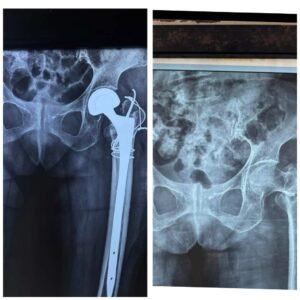

рд╕рдбрд╝рдХ рджреБрд░реНрдШрдЯрдирд╛ рдореЗрдВ рдЧрдВрднреАрд░ рд░реВрдк рд╕реЗ рдШрд╛рдпрд▓ 90 рд╡рд░реНрд╖реАрдп рдЗрдВрдбрд┐рдпрд╛ рдмрд╛рдИ рдХреЗ рдмрд╛рдПрдВ рдХреВрд▓реНрд╣реЗ рдХреА рд╣рдбреНрдбреА рдмреБрд░реА рддрд░рд╣ рдХреНрд╖рддрд┐рдЧреНрд░рд╕реНрдд рд╣реЛ рдЧрдИ рдереАред рдкрд░рд┐рдЬрди рдЙрдиреНрд╣реЗрдВ рддрддреНрдХрд╛рд▓ рд╕рд┐рдореНрд╕ (CIMS) рдХреЗ рдЕрд╕реНрдерд┐ рд░реЛрдЧ рд╡рд┐рднрд╛рдЧ рд▓реЗрдХрд░ рдкрд╣реБрдВрдЪреЗ, рдЬрд╣рд╛рдВ рд╡рд┐рд╢реЗрд╖рдЬреНрдЮ рдЪрд┐рдХрд┐рддреНрд╕рдХреЛрдВ рдХреА рдЯреАрдо рдиреЗ рдЙрдиреНрдирдд рддрдХрдиреАрдХ рд╕реЗ рдЬрдЯрд┐рд▓ рд╕рд░реНрдЬрд░реА рдХрд░ рдЙрдиреНрд╣реЗрдВ рдирдпрд╛ рдЬреАрд╡рди рдкреНрд░рджрд╛рди рдХрд┐рдпрд╛ред

рдЕрд╕реНрдерд┐ рд░реЛрдЧ рд╡рд┐рд╢реЗрд╖рдЬреНрдЮ рдбреЙ. рддрд░реБрдг рд╕рд┐рдВрд╣ рдиреЗ рдмрддрд╛рдпрд╛ рдХрд┐ рдЗрд╕ рдЖрдпреБ рдореЗрдВ рдХреВрд▓реНрд╣реЗ рдХрд╛ рдлреНрд░реИрдХреНрдЪрд░ рд╕рд╛рдорд╛рдиреНрдп рд░реВрдк рд╕реЗ рдЬреБрдбрд╝ рдкрд╛рдирд╛ рдмреЗрд╣рдж рдХрдард┐рди рд╣реЛрддрд╛ рд╣реИред рд▓рдВрдмреЗ рд╕рдордп рддрдХ рдмрд┐рд╕реНрддрд░ рдкрд░ рд░рд╣рдиреЗ рд╕реЗ рд╕рдВрдХреНрд░рдордг, рдХрдордЬреЛрд░реА рдФрд░ рдЕрдиреНрдп рдЬрдЯрд┐рд▓рддрд╛рдУрдВ рдХрд╛ рдЦрддрд░рд╛ рдмрдврд╝ рдЬрд╛рддрд╛ рд╣реИред рдорд░реАрдЬ рдХреА рд╕реНрдерд┐рддрд┐ рдХреЛ рджреЗрдЦрддреЗ рд╣реБрдП рд╡рд┐рднрд╛рдЧрд╛рдзреНрдпрдХреНрд╖ рдбреЙ. рдмреЗрди рдХреЗ рдорд╛рд░реНрдЧрджрд░реНрд╢рди рдореЗрдВ рдЪрд┐рдХрд┐рддреНрд╕рдХреЛрдВ рдХреА рдЯреАрдо рдиреЗ рд▓рдВрдмреЗ рд╕реНрдЯреЗрдо рд╡рд╛рд▓реЗ рдореЙрдбреНрдпреВрд▓рд░ рдмрд╛рдЗрдкреЛрд▓рд░ рдХреГрддреНрд░рд┐рдо рдХреВрд▓реНрд╣рд╛ рдкреНрд░рддреНрдпрд╛рд░реЛрдкрдг рдХреЗ рд╕рд╛рде рдЯреАрдмреАрдбрдмреНрд▓реНрдпреВ рддрдХрдиреАрдХ рдФрд░ рдПрдиреНрдХреНрд▓реЗрдЬ рд╡рд╛рдпрд░рд┐рдВрдЧ рдХрд╛ рдЙрдкрдпреЛрдЧ рдХрд░ рд╕рдлрд▓ рдСрдкрд░реЗрд╢рди рдХрд┐рдпрд╛ред

рд╕рд░реНрдЬрд░реА рдХреА рд╕рдлрд▓рддрд╛ рдХрд╛ рдкрд░рд┐рдгрд╛рдо рдпрд╣ рд░рд╣рд╛ рдХрд┐ рдорд░реАрдЬ рдореЗрдВ рддреЗрдЬреА рд╕реЗ рд╕реБрдзрд╛рд░ рд╣реБрдЖ рдФрд░ рдСрдкрд░реЗрд╢рди рдХреЗ рдЕрдЧрд▓реЗ рд╣реА рджрд┐рди рд╡рд╣ рдЕрдкрдиреЗ рдкреИрд░реЛрдВ рдкрд░ рдЦрдбрд╝реА рд╣реЛрдХрд░ рдЪрд▓рдиреЗ рд▓рдЧреАрдВред рдЗрд╕ рдЙрдореНрд░ рдореЗрдВ рдЗрддрдиреА рд╢реАрдШреНрд░ рд░рд┐рдХрд╡рд░реА рдХреЛ рдЪрд┐рдХрд┐рддреНрд╕рд╛ рдХреНрд╖реЗрддреНрд░ рдореЗрдВ рдмрдбрд╝реА рдЙрдкрд▓рдмреНрдзрд┐ рдорд╛рдирд╛ рдЬрд╛ рд░рд╣рд╛ рд╣реИред